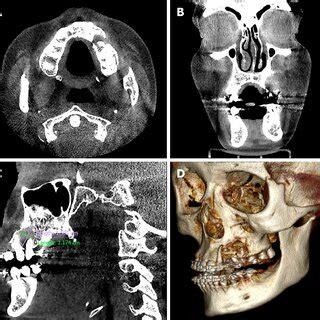

Tridimensional Reconstruction Of Computerized Tomograph 3d A

Exploring 3D Reconstruction in Tomography